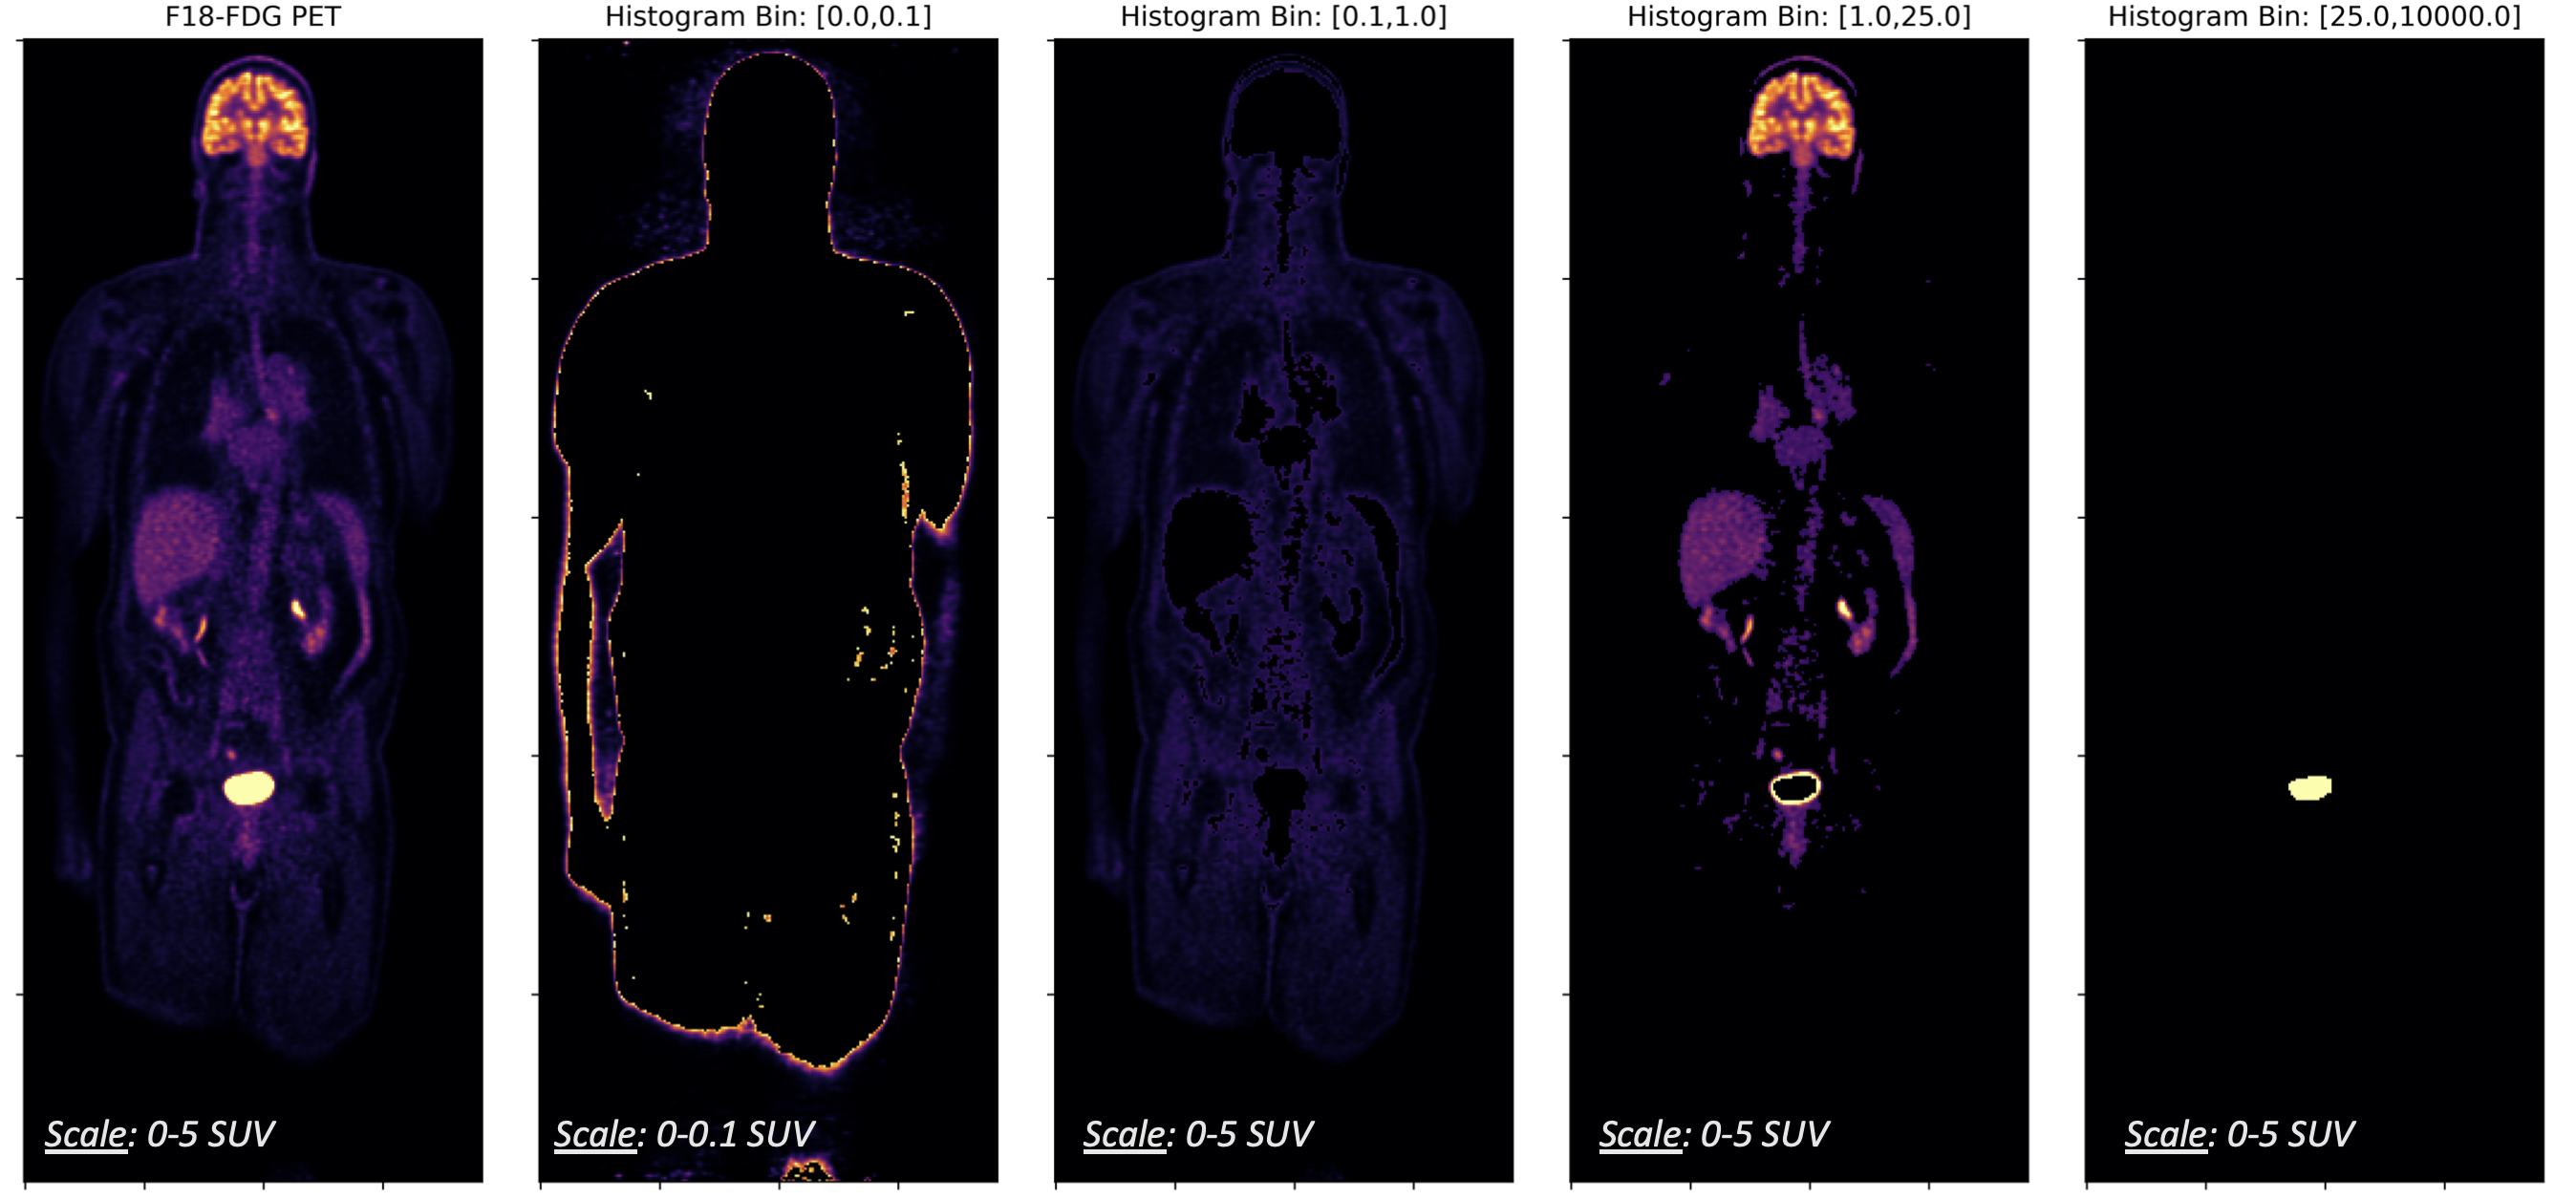

2.3 Learning

One of the primary challenges with domain translation of MRI to PET is maintaining high accuracy across the full dynamic range of PET. Although SUV-scaling does provide a more consistent and intuitive numerical range, we find that explicit control in the objective function is required to prevent smoothing over suitable minima. For example, the histogram distribution of a whole-body 18F-FDG-PET exam (Fig. 2) reveals that different tissues differ in amount of physiologic uptake. For example, in the lungs, heart, and liver there is often increased activity between SUV, and in regions such as the bladder and brain the recorded SUV can be greater than 20. In particular, since we are interested in using the predictions of our model for PET quantification studies, we require high accuracy across all relevant scales. This precludes the use of simple -norm objective functions, such as the mean absolute error (MAE), that may be dominated by the high absolute or relative error in one or more histogram bins.

where is the conventional voxel-wise absolute error, is the MRI input volume, is the groundtruth PET volume, and represents the predicted synthetic sPET. In Equation 2, represents an indicator variable selecting the voxels belonging to bin of the -bin histogram of , and is chosen as 1e-3 to prevent overflow. The histogram bins (Fig. 2) and corresponding weights (, ) were chosen based on empirical observation to prevent domination of by high absolute errors in high-SUV regions or by high relative errors in low-SUV regions. The intention of this flexible formulation with and is to define a family of functionals that can be tailored to different patient datasets, PET tracers, and anatomic regions.